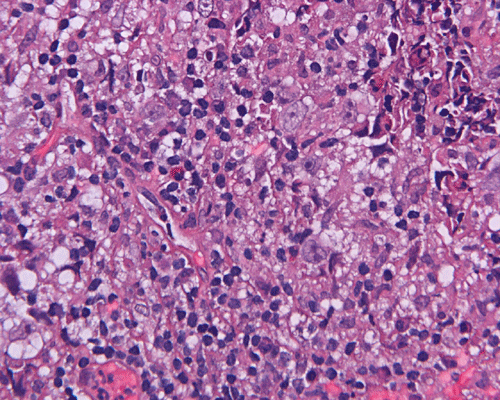

Paraffin sections: The entire volume of the tissue is made up of a granulomatous inflammation with poorly formed granuloma (Panel F, G, and H). The density of the lymphocytes is variable in different areas. In some areas, there is a rather intense lymphocytic infiltration accompanied by scant atypical cells with enlarged nulcei and prominent nucleoli (arrows in Panel I and J, Panel J is a higher magnification of Panel I). These atypical cells are quite easy to be missed. No microorganisms were identified by acid fast stain, PAS stain or GMS stain. The lymphocytes but not the atypical cells are positive for CD20 (Panel K) or CD3 (Panel L). The granulomatous background is strongly positive for CD68 (Panel M). Only rather faint positive staining for placental alkaline phosphatase (PLAP) is demonstrated and the interpretation is difficult as they are present in areas with crush artifact (Panel N). Many of the large, atypical cells are positive for CD117 (c-kit) (Panel O).

Intracranial germinoma is histologically identical to ovarian dysgerminoma and testicular seminoma. There is a tendency to infiltrate adjacent structures and to spread throughout the ependyma, the ventricular system and subarachnoid spaces. Microscopically, they consist of nests, lobules, cords, and/or sheets of large round tumor cells with well-defined borders, clear to pale cytoplasm with artifactual vacuolization, round and centrally located nuclei with open chromatin and prominent round or bar-shaped nucleoli. The cytoplasm is glycogen-rich, making these cells periodic acid-Schiff (PAS)–positive and diastase sensitive. These tumor cells are mitotically active. Atypical mitosis, however, is not a common finding. Necrosis is usually not prominent.  In the most classic histologic picture, clusters and cords of large germinoma cells are separated by a dense, lymphocytic infiltration admixed with some macrophages and a delicate fibrovascular network. Plasma cells may be found. At medium-power magnification with hematoxylin and eosin stain, the contrast between the smaller, darkly staining lymphocytes and the larger, pale staining cytoplasm of neoplastic cells is virtually pathognomonic. The amount of inflammatory cells can have wide variations among different tumors. In some occasions, the large germinoma cells are difficult to be found and the overall picture may suggest a lymphoma. Syncytiotrophoblastic cells can also be present. These cells should not be mistaken as evidence of choriocarcarcinoma.

Germinomas can elicit an atypical gliosis in the surrounding glial tissue which may be confused with malignant glial neoplasms. This is true particularly of specimens taken from the periphery of the germinoma. The tumor may appear as a desmoplastic tumor. The inflammatory response may be problematic in reaching a histologic diagnosis, especially in small biopsies, as macrophages can be difficult to distinguish from a non-seminomatous neoplastic component.

Granulomatous changes are common findings in germinomas and intracranial germinomas follow this general trend 3, 4, 5. It can be extensive. This feature is particularly problematic in neuropathologic when stereotactic biopsy is performed and the amount of tissue available for examination is limited as illustrated in this case. During intraoperative consultations, a frozen section diagnosis of granulomatous inflammation should prompt additional sampling as isolated granulomatous inflammation of infectious origin and sarcodosis are quite uncommon in the pineal gland.